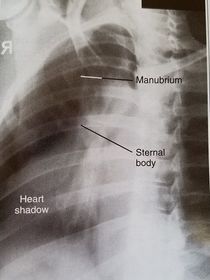

| RAO Sternum | ANATOMY: jugular notch, SC joints, sternal body, and xiphoid process CRITERIA: sternum projected within heart shadow next to vertebral column POSITIONING: pt. rotated 15-20 degrees breathing technique CR perpendicular @ midsternum (2 fingers off downside spine) |

| Lateral Sternum | ANATOMY: manubrium, sternal body, and xiphoid in profile CRITERIA: 72'' SID reduces OID arms must be behind pt's back POSITIONING: CR perpendicular @ midsternum |